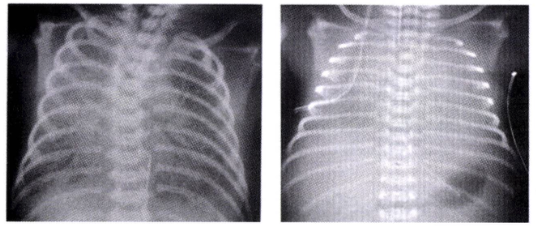

• CXR 상 다음과 같은 전형적인 소견을 확인

• 미만성 망상 과립상 음영 (Diffuse reticulogranular pattern)

• 공기 기관지 조영상 (Air-bronchogram)

• 전체적인 폐 용적 감소 (Low lung volume): 폐가 충분히 팽창하지 못해 전반적으로 하얗고 작아 보임 (저팽창, hypoaeration)

• 심하게 진행된 경우 폐 전체가 완전히 하얗게 보이는 white out 소견을 보일 수 있음

• 치료: 폐표면활성제 투여 + 호흡보조요법

• 폐표면활성제 보충 요법 (Surfactant Replacement Therapy)

• 기관내관을 통해 폐에 직접 surfactant를 투여